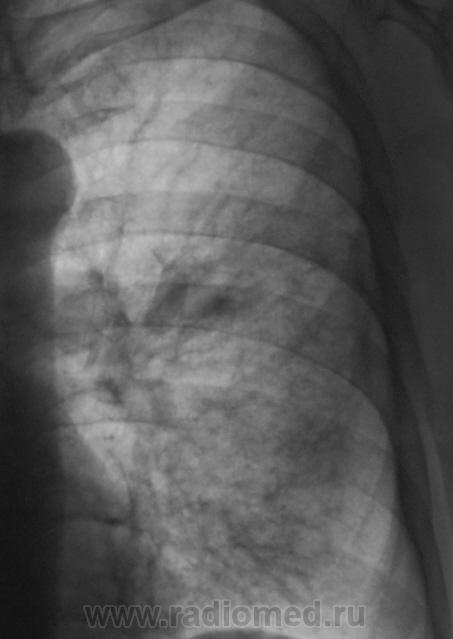

При расшифровке флюорограмм пациент "взят на контроль". Жалоб пациент не предъявляет. Подняли "архив", флюорограмма за 2009 г. - "норма".

Произвели стандартное дообследование.

Томограммы.

tbc

А, какой ТВС?